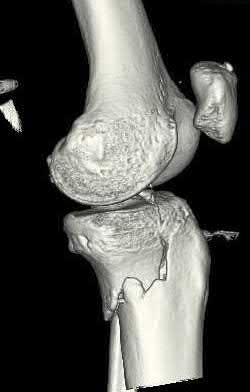

A 38-year-old male suffers the injury shown in Figure A. During operative fixation, free osteoarticular fragments are encountered and reconstruction of these pieces is attempted. Postoperatively, which of the following will have the most beneficial effect on the healing potential of the surviving chondrocytes within these reconstructed articular segments?

Figure A demonstrates a comminuted tibial plateau fracture with significant intra-articular involvement. Basic science evidence has demonstrated that post-operative gentle compressive loading may have a positive impact on articular cartilage healing; however, excessive shear loading may be detrimental.

Irrgang et al provide guidelines for rehabilitation following surgical management of articular cartilage lesions of the knee. They state that after articular cartilage repair, exercises to enhance muscle function must be done in a manner which minimizes shear loading of the joint surfaces in the area of the lesion. The authors also discuss the benefits of gentle compressive loading and motion of the joint, and its positive effects on chondrocyte nutrition.

Furthermore, they recommend a period of protected weight bearing as often being necessary, and that this should be followed by progressive loading of the joint.

Illustration A is a diagram showing the different layers of joint cartilage.